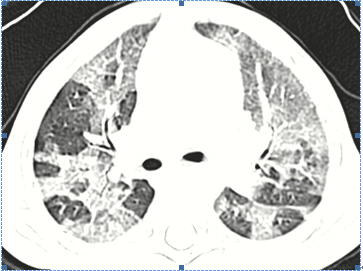

1、壞死性肺炎定義?壞死性肺炎是侵襲性肺炎的并發(fā)癥,其特征為實變區(qū)域內(nèi)出現(xiàn)壞死病灶;2、壞死性肺炎的常見病原體?細菌、支原體、真菌、結核桿菌、病毒(H1N1流感病毒);3、兒童壞死性肺炎的病因有哪些?1)肺炎鏈球菌壞死性肺炎:肺炎鏈球菌引起的壞死性肺炎并胸腔積液增多,多數(shù)為3歲以下嬰幼兒,表現(xiàn)為高熱、咳嗽,肺部有固定性濕性羅音,初期胸片或CT表現(xiàn)為大葉肺實變,約在1-2周肺實變區(qū)出現(xiàn)多發(fā)的小空洞并膿胸,炎性指標如外周血WBC和N↑↑,CRP常>100mg/L,痰液、胸水肺炎鏈球菌培養(yǎng)陽性,一些病例血培養(yǎng)陽性,胸水檢查為膿胸表現(xiàn),后期有肺大泡或氣胸,一些發(fā)生支氣管胸膜瘺;2)金黃色葡萄球菌壞死性肺炎(SA-NP):發(fā)熱、呼吸窘迫、有膿痰、可咯血、病情重、可進展迅速、伴發(fā)休克常見,病死率較高、白細胞降低(PVL殺白細胞素-陽性的SA)、易于合并其他部位的感染(皮膚、軟組織等);3)CA-MRSA:突出表現(xiàn)為皮膚和軟組織感染,多位于上下肢,共同特征為多部位受累,包括肺炎伴膿胸、骨髓炎、關節(jié)炎、皮膚、心內(nèi)膜炎,可有爆發(fā)性紫癜,死亡和PVL產(chǎn)生有關,發(fā)生于健康的青少年和學生,前期可有肢體疼痛,迅速出現(xiàn)高熱、咳嗽,因病理表現(xiàn)為急進性出血壞死性肺炎,可出現(xiàn)痰中帶血或咯血,同時出現(xiàn)膿毒血癥表現(xiàn)如明顯中毒癥狀,呼吸增快、心率增快,C反應蛋白增高,因PVL產(chǎn)生,白細胞可減少。影像學表現(xiàn)為多葉肺泡浸潤或高密度實變,迅速出現(xiàn)空腔和膿胸或膿氣胸;4)化膿性鏈球菌:臨床表現(xiàn)為皮疹、脫皮,壞死性肺炎并胸腔積液,鏈球菌感染中毒休克綜合征,耐藥報道少;5)難治性肺炎支原體:(1)病情重:合理大環(huán)內(nèi)酯類抗生素治療后仍持續(xù)高熱、劇烈咳嗽;(2)雙側或單側大葉肺實變,合并少-中量胸腔積液;(3)易合并肺外表現(xiàn);?(4)炎性指標升高:中性粒細胞、血沉和CRP升高,血凝指標也升高;??(5)患兒病情重(除肺部嚴重病變外尚可有多系統(tǒng)肺外損害);?(6)遷延不愈者(病程常大于4周)遺留肺部后遺癥;6)侵襲性肺曲霉?。簤乃佬苑窝??有基礎肺疾病和原發(fā)免疫功能障礙,靠近胸膜結節(jié)實變,有空洞形成,伴胸膜受累;7)干酪性肺炎:原發(fā)性肺結核惡化,可多發(fā)空洞,可有支氣管播散。

1、什么是閉塞性細支氣管炎?閉塞性細支氣管炎(Bronchiolitisobliterans,BO)是與細支氣管炎癥和免疫反應損傷相關,導致管腔閉塞的慢性氣流阻塞綜合征??珊喜⒅夤軗p害,出現(xiàn)閉塞、擴張;2、閉塞性細支氣管炎的臨床類型有哪些?1)縮窄性細支氣管炎:經(jīng)典BO(constrictiveBO),粘膜下或外周炎性細胞浸潤和纖維化,致細支氣管腔受壓狹窄,管腔內(nèi)無肉芽組織形成;2)增殖性細支氣管炎:(proliferativeBO),細支氣管腔內(nèi)肉芽組織增生引起管腔狹窄,主要在呼吸性細支氣管,可累積肺泡;二種類型可混合存在,尤其是感染后;3、閉塞性細支氣管炎的病因是什么?病毒(腺病毒、流感病毒、麻疹病毒),細菌(金葡菌、B族溶血性鏈球菌、肺炎鏈球菌),肺炎支原體;多是多病原混合感染,如腺病毒合并其他病毒,合并真菌:曲霉菌的定植及感染,合并細菌:銅綠假單胞菌的定植及感染,其次合并其他因素:如胃食道返流等、毒氣的吸入、異物吸入等;結締組織病、自身免疫性溶血、骨髓和心肺移植、類風濕性關節(jié)炎、滲出性多形性紅斑、藥物、腫瘤等;4、閉塞性細支氣管炎的臨床表現(xiàn)有哪些?咳嗽、喘息、呼吸困難、運動不耐受、短暫的癥狀改善期后加重和持續(xù)、喘鳴音“crackles”音;5、什么是馬賽克灌注征?馬賽克灌注(mosaicperfusion),是指肺密度減低區(qū)與肺密度增高區(qū)夾雜相間呈不規(guī)則的補丁狀或地圖狀分布的表現(xiàn);6、BO的臨床診斷要點有哪些?(1)急性感染或急性肺損傷后6周以上的反復或持續(xù)氣促,喘息或咳嗽、喘鳴;(2)肺CT顯示支氣管壁增厚,支氣管擴張,肺不張,馬賽克灌注征、血管衰減;(3)肺功能示阻塞性通氣功能障礙;(4)排除其他阻塞性疾病,如哮喘、先天纖毛運動功能障礙、囊性纖維化、異物吸入、先天發(fā)育異常、結核、彌漫性泛細支氣管炎、持續(xù)性細菌性細支氣管炎、間質性肺炎等;7、出現(xiàn)什么情況需要考慮得了閉塞性細支氣管炎?l急性肺炎后持續(xù)咳嗽、喘息;l嚴重的急性呼吸道感染后長時間存在喘鳴音“crackles”;l急性肺損傷后長期運動不耐受;l胃內(nèi)容物的反復吸入;l急性肺炎后6周出現(xiàn)透明肺綜合征;lSJS后一段時間出現(xiàn)持續(xù)咳嗽、喘息;8、得了閉塞性細支氣管炎有什么治療辦法呢?激素、大環(huán)內(nèi)酯類、支氣管擴張劑、孟魯司特等,重視支氣管擴張治療(導致感染,加重病情),三聯(lián)治療(抗生素+粘液溶解劑+免疫增強劑),重視哮喘治療(包括避免過敏原),重視感染的治療(長期預防)。